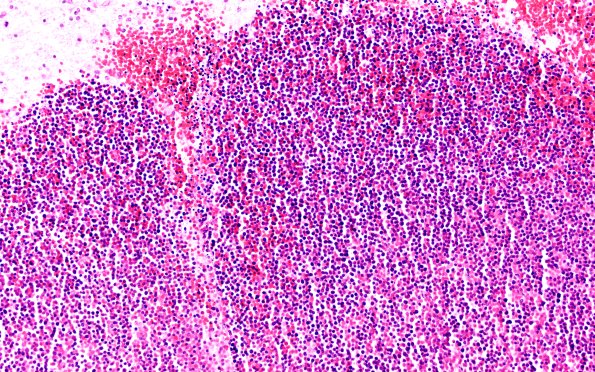

Washington University Experience | NEOPLASMS (HEMATOLYMPHOID) | Granulocytic Sarcoma | 1B3 (Case 1) E 20X

Progressively increasing magnification of the constituent elements of leukemic nodules showing aggregates of myeloblasts, many with granular cytoplasm. (H&E)